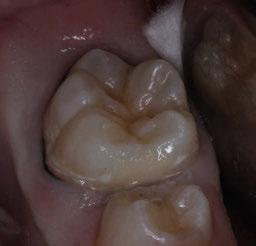

Figura 3. Visión intraoral oclusal mandibular. Figura 4. Visión intraoral frontal. Figura 1. Visión intraoral oclusal maxilar. Figura 2. Visión lateral izquierda intraoral. Figura 7. Escaneado intraoral maxilar con Dexis IS3700. Figura 8. Escaneado intraoral mandibular con Dexis IS3700. Figura 5. Visión extraoral lateral sonrisa.